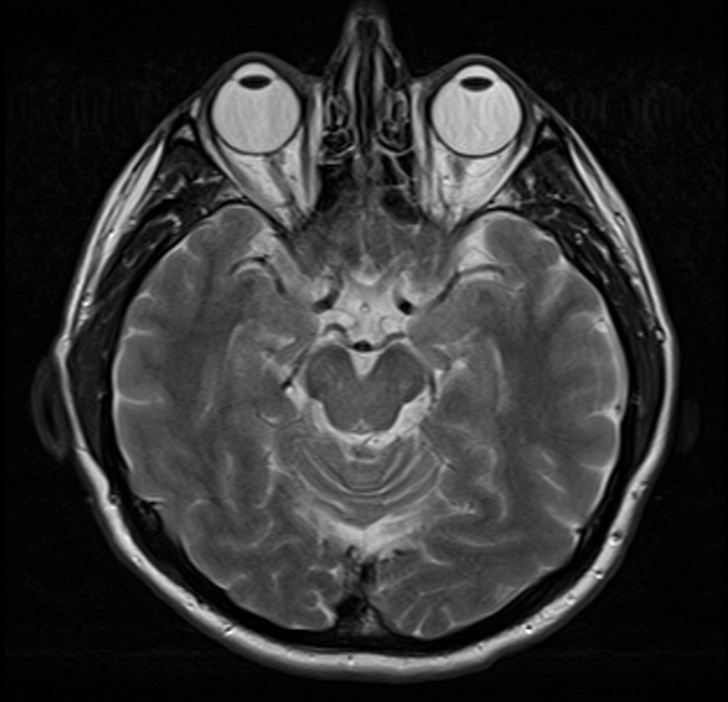

Napriek tomu si nie sú úplne vedomí všetkých procesov, ktoré prebiehajú v v našom tele dokonca ani špičkoví vedci. Pomáhajú im obrázky nielen z röntgenu, ale aj z počítačovej tomografie, ktorú poznáme pod skratkou CT, alebo z magnetickej rezonancie, ktorá má zase skratku MRI. Tu sú fotografie práve z týchto prístrojov, ktoré nám približujú, ako funguje ľudské telo.

7. Magnetická rezonancia zdravého ľudského mozgu